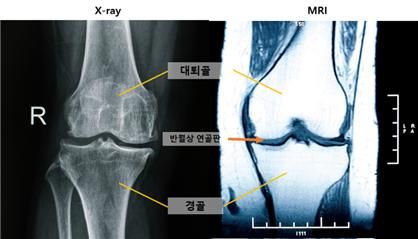

(사진 : 엑스레이 및 MRI 무릎 사진)

엑스레이에서 정상으로 진단된 무릎이라도 MRI에서 ‘중앙 대퇴골 연골 손상’ 소견이 관찰된다면 무릎 관절염이 이미 진행되고 있을 가능성이 높다는 사실이 규명했다.

또한 MRI로 ‘내측 반월상 연골 돌출’이 관찰되면 관절염이 심각해질 위험이 높은 것으로 나타났다.

이 손상은 엑스레이에서 정상으로 여겨지는 관절염 0기부터 관찰돼 MRI가 무릎 관절염 초기 변화를 확인하는 데 중요한 도구임을 보여줬다.

관절염 진행에 따라 MRI상 무릎 중앙에서는 연골·반월상 연골판·뼈, 후방에서는 반월상 연골판·연골·뼈 순서로 손상 양상에 차이가 있었다.